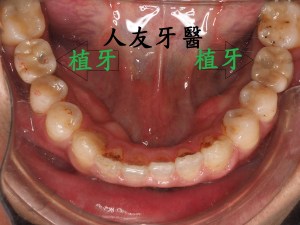

植牙後常見的問題,人工植牙雖然有著不會蛀的金屬質地,但它附屬的地基「齒槽骨」和周圍覆蓋的牙肉跟我們自己的牙齒一樣,植牙周圍若是清潔不乾淨,也會產生牙周病,造成「植體周圍炎」。

但尚未影響到硬組織,被稱為植體周圍黏膜炎;若已破壞到周遭骨頭,被稱為植體周圍炎。若周遭骨被破壞,最後可能造成植體失敗,需要移除,植牙等於做了白工。分析造成植體周圍疾病的原因,主要是細菌,如牙菌斑;咬合力量過大、牙套完成時殘留的黏著劑未清潔乾淨、製作不當的牙套也會。

植體周圍炎牙齒從外表看不出來,需從x光片才能看出來,為避免造成植體周圍組織發炎,甚至破壞到周遭骨頭,平時應注重牙齒清潔保養,選擇刷毛軟的牙刷清潔 , 搭配牙間刷去清潔牙縫 , 並定期回診檢查,確保牙齒健康。